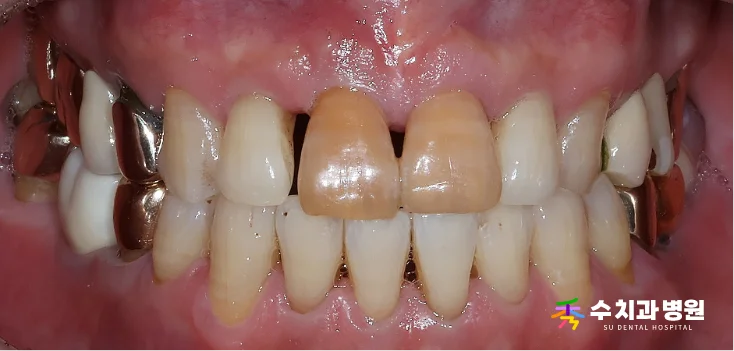

📸 치료 전후 비교 (Before & After)

[치료 전후 비교 사진] (촬영일: 전 2025년 06월 / 후 2025년 09월)

흔들리는 앞니는 튼튼한 앞니도,

변색된 옆 치아는 심미적인 새 치아로 교체되었습니다.

좌우 대칭이 맞아 웃는 모습이 자연스럽습니다.